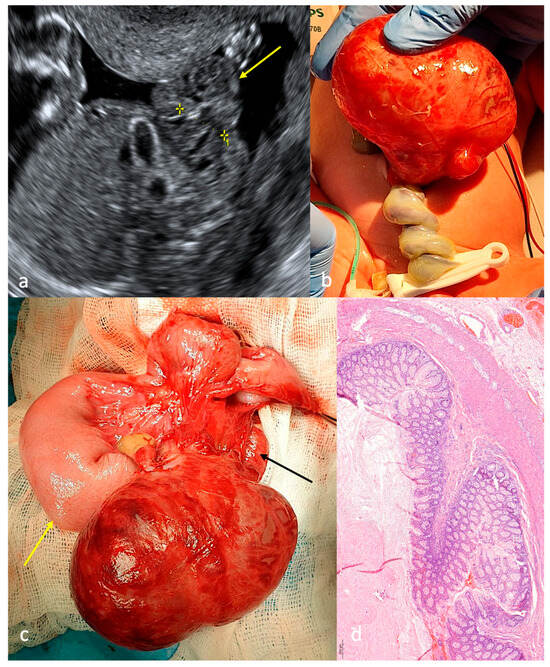

Closing/Closed Gastroschisis (CGS): Antenatal Predictors and Surgical Strategies in Cases of Unique Anatomy from a Case Series

Background: Closing/closed gastroschisis (CGS) accounts for approximately 6% of gastroschisis cases globally. Currently, no consensus exists regarding: antenatal predictors of CGS types, optimal antenatal management (ultrasound screening frequency, indications for early delivery), or standardized surgical strategies tailored to CGS type (staging/timing of [...] Read more.

Background: Closing/closed gastroschisis (CGS) accounts for approximately 6% of gastroschisis cases globally. Currently, no consensus exists regarding: antenatal predictors of CGS types, optimal antenatal management (ultrasound screening frequency, indications for early delivery), or standardized surgical strategies tailored to CGS type (staging/timing of procedures, enterostomy necessity/level). Methods: Five neonates with CGS were enrolled and classified according to Perrone’s classification: two patients with type B (40%), one with type C (20%), one with type D (20%), one patient was classified as unclear (20%). Gender distribution—80% female (n = 4), 20% male (n = 1); gestational age—median 35 weeks (IQR 35–38); preterm birth rate—80% (n = 4); birth weight—median 2620 g (IQR 2310–3850). Results: Three patients (60%) developed antenatal intestinal obstruction signs at the third trimester, including two who postnatally demonstrated viable intestinal loops. Two patients (40%) with necrosis of eviscerated intestine demonstrated onset of antenatal intestinal obstruction signs at the second trimester. Patients with CGS type B were managed using a staged surgical approach; patients with types C and D received single-stage repair. Patient with CGS type B achieved complete clinical recovery. Three patients (60%) with CGS types C and D developed short bowel syndrome. Conclusions: The appearance of sonographic signs of intestinal obstruction in the second trimester may be a predictor for a high risk of subsequent significant vascular compromise of the eviscerated bowel, leading to more severe types of CGS (C and D). For patients with CGS type B, a staged surgical approach is advisable to maximize bowel length preservation. Full article

Show Figures

Figure 1